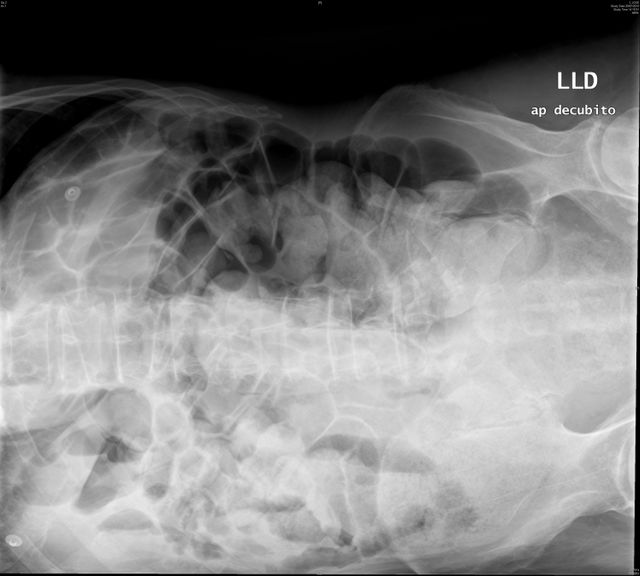

Suboclusión intestinal.